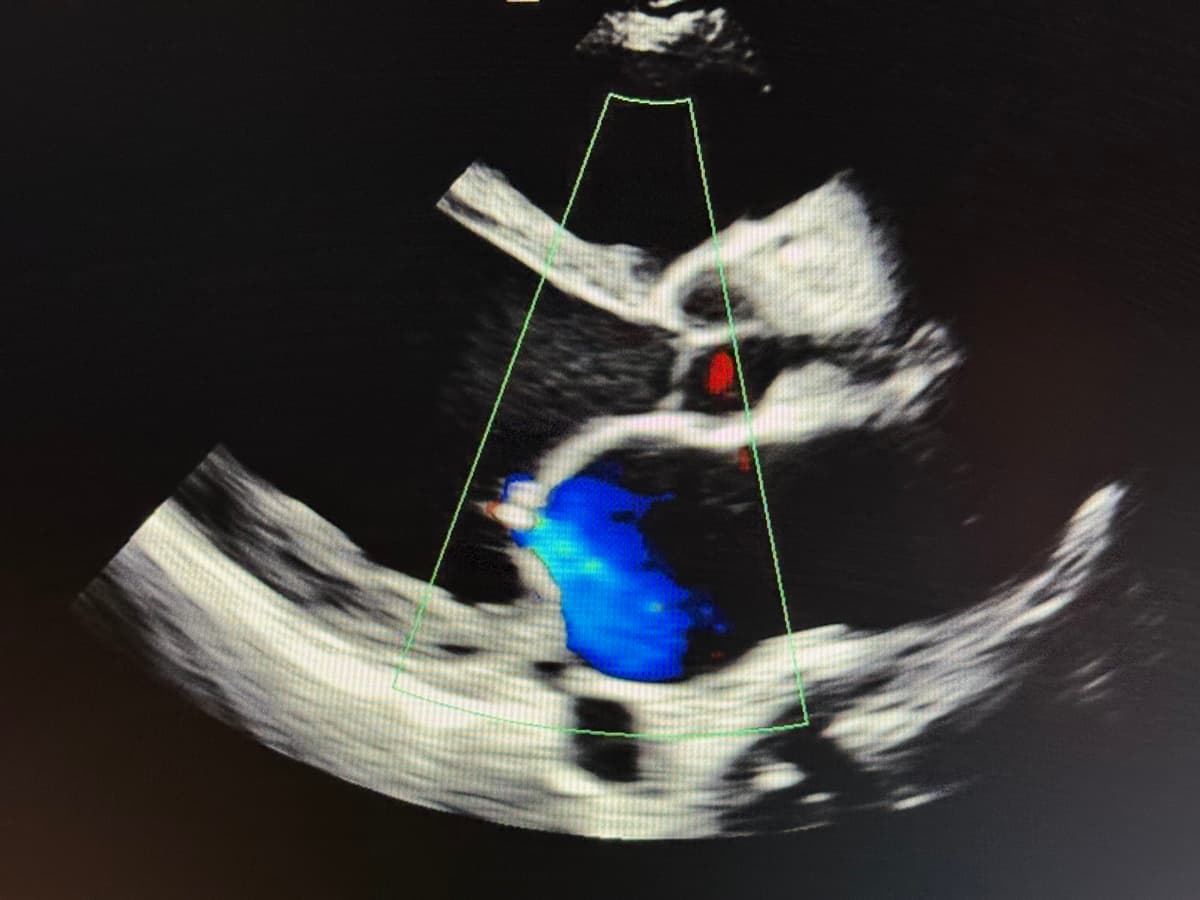

- Echocardiogram